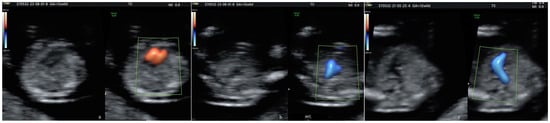

- A normal 4-chamber view and normal equal ventricular inflows in a normal case.

- Confluence of the arches on the left (“the V-sign” in the 3VT view) in a normal case.

- The “reverse boomerang sign”—the reverse curvature of the right ventricle outflow tract (RVOT) at the level of the 3VT view in a TGA case.